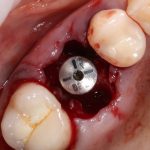

Так вот, чрезмерная атрофия альвеолярного гребня может лишить нас возможности имплантации — нам просто не хватит объемов костной ткани для нормальной установки имплантов. Однако, эта проблема решаема — существует целый ряд методик остеопластики (включая синуслифтинг), позволяющих восстановить любой объем костной ткани в в любом участке зубного ряда с высокой степенью эффективности. И, как правило, хорошие врачи в хороших клиниках так и поступают:

Увы, но подобные методики подходят не всем. Скажем так, я бы десять раз подумал прежде, чем проводить остеопластику пациенту, которому больше 80 лет, у которого есть серьезные проблемы со здоровьем. Также было бы сложно восстановить до необходимого полностью беззубый альвеолярный гребень со значительной атрофией по высоте:

Их можно установить в минимально возможный объем костной ткани, где установка обычных взрослых имплантов невозможна без предварительной остеопластики. В некоторых случаях они даже позволяют избежать синуслифтинга, что, согласитесь, звучит очень заманчиво.

Другими словами, уважаемые друзья, ультракороткие импланты призваны сделать нашу работу проще. Мы реально получаем шанс избежать сложной остеопластики, в некоторых случаях — открытого синуслифтинга, которым любят пугать некоторые фанаты с ультракороткими писюнами.